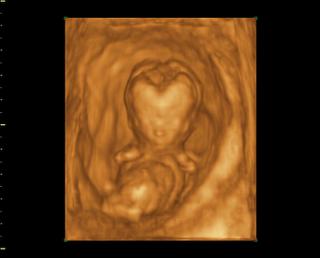

Tak čaute kočky, som doma z 3Dčka, dnes som 14+1 mám plno krásnych fotiek na kľúči, najbližšie mám prísť na 3Dčko v 20tt a potom tretí krát okolo 25 tt a vtedy dostanem aj DVDčko zo všetkých troch UV. Ale fotky aj videá nám dal na USB kľúč takže už teraz mám všetky 🙂 Čo sa pohlavia týka, tak to vyzerá na chlapca, ešte mám aj jednu fotku kde to zreteľne vidieť že to bude asi chlapec. bábo bolo aktívne strašne veľa skákalo a pohybovalo sa, stále si rúčkami chytalo hlavičku (to robí aj Danko stále 😀 ) Priateľ bol vnútri so mnou takže to celé videl.